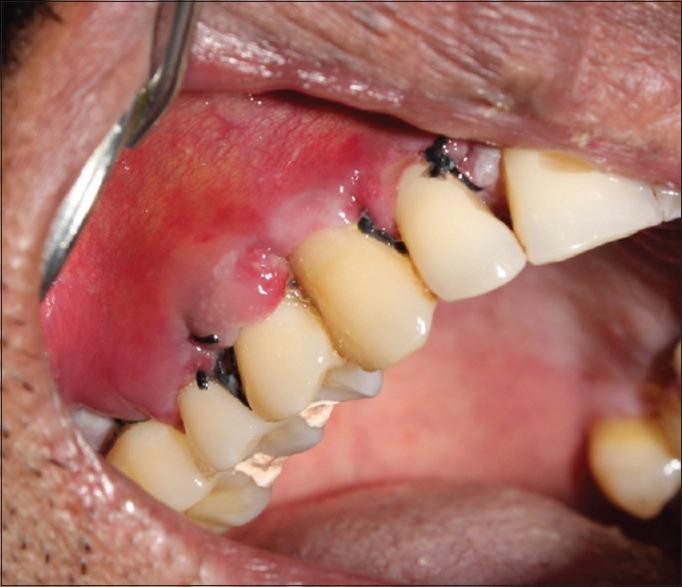

Nowadays, patients are much concerned about esthetics of the oro-facial region. Gingival recession is considered as one of the major esthetic problems creating complex situations by compromising oral esthetics. This can be treated successfully by means of several mucogingival surgical procedures which can be used to accomplish satisfactory root coverage without any loss of interdental soft- and hard-tissue height. Grafts are also very useful in such scenarios. Our case reports the connective tissue graft technique used in the treatment of gingival recession. The objective of this case was to evaluate the efficacy of connective tissue graft (CTG) and also to mention the management of complications on the donor site.